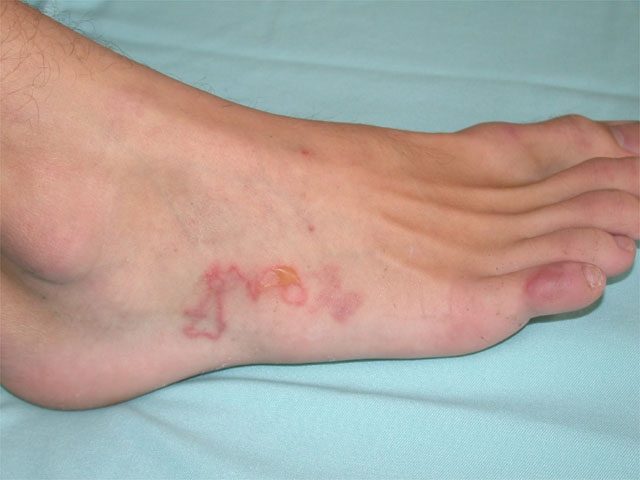

Chlamydia

Besides peripheral oligoarthritis, common manifestations include enthesitis, conjunctivitis, urethritis, oral ulcers, and keratoderma blennorrhagicum:

Cutaneous Larva Migrans

Cutaneous larva migrans (CLM) is a creeping cutaneous eruption caused by dog (Ancylostoma caninum) or cat (A braziliense) hookworm larvae. Most infections are acquired from walking barefoot on contaminated sand (beaches) or soil. Humans are incidental hosts, and larvae are typically unable to penetrate the dermal basement membrane. As a result, cutaneous infection without deeper penetration is the norm.

Most infections occur in the lower extremities (70%), and symptoms usually start with a pruritic, erythematous papule at the site of larvae penetration (which may go unnoticed). Within a few days, patients develop symptoms related to larvae migration: intensely pruritic, serpiginous, reddish-brown cutaneous tracks. Although most cases resolve spontaneously after a few weeks, antihelmintics (eg, ivermectin) are usually given to aid clearance.